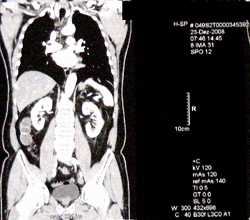

Anatomie: Alter Mann möchte helfen (Foto: pixelio.de, Hartmut910) |